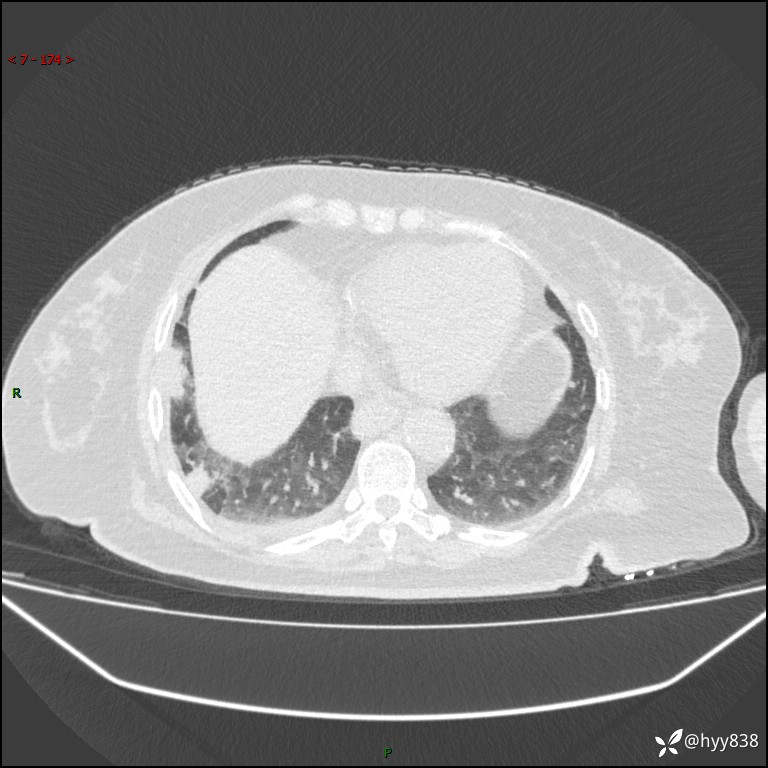

患者性别:女

患者年龄:57岁

简要病史:昏迷入院

临床诊断:昏迷

胸部 CT平扫、